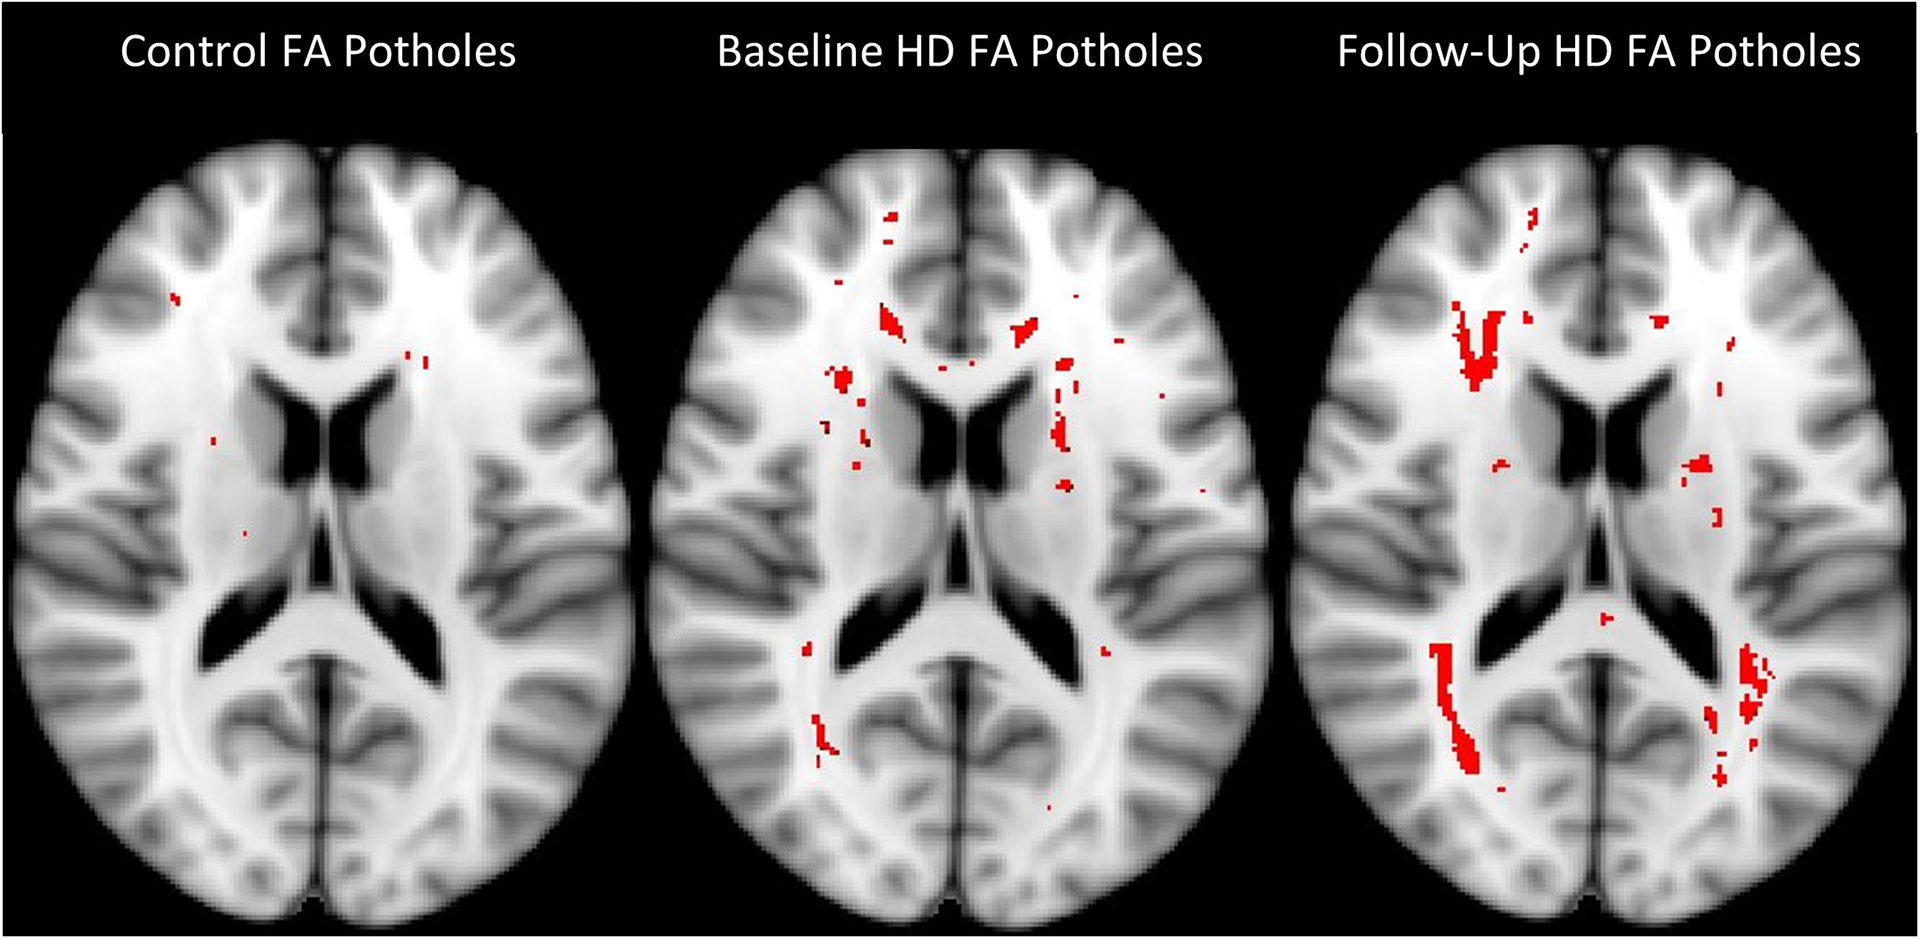

We collected anatomical and diffusion MRIs as well as cognitive testing from in-center hemodialysis patients at baseline and one year later. Gray matter thickness, white matter volume, and white matter diffusion tensor imaging parameters were measured to identify longitudinal changes. We analyzed the diffusion tensor imaging parameters by averaging the whole white matter and using a pothole analysis. 18 hemodialysis patients were included in the longitudinal analysis and 15 controls were used for the pothole analysis. We used the NIH Toolbox Cognition Battery to assess cognitive performance over the same time frame.

Over the course of a year on hemodialysis, we found a decrease in white matter fractional anisotropy across the entire white matter (p < 0.01), and an increase in the number of white matter fractional anisotropy voxels below pothole threshold (p = 0.03). We did not find any relationship between changes in whole brain structural parameters and cognitive performance.